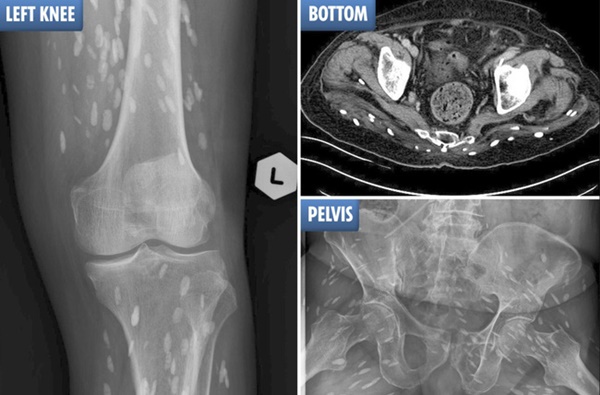

Trong các hình chụp siêu âm, X-quang, có thể nhận ra vô số trứng sán dây (sán xơ mít) cư trú trong cơ thể người đàn ông. Bệnh nhân này đặc biệt thích ăn 2 loại thịt.

Trong các hình chụp siêu âm, X-quang, có thể nhận ra vô số trứng sán dây (sán xơ mít) cư trú trong cơ thể người đàn ông 74 tuổi. Bệnh nhân này đặc biệt thích ăn thịt lợn và thịt bò tái.

Bác sĩ lập tức chỉ định chụp cộng hưởng từ, chụp cắt lớp vi tính và chụp X-quang cho bệnh nhân. Kết quả, các bác sĩ vô cùng kinh sợ khi phát hiện hàng trăm trứng sán dây nhỏ xíu lúc nhúc trong gần như mọi phần trong cơ thể người bệnh.

Qua hình ảnh chụp chiếu, dễ dàng nhận ra trứng sán dây xuất hiện trong não, cột sống, mông, cổ, ngực và chân cụ ông đã về hưu. Cụ được chẩn đoán mắc bệnh ấu trùng sán lợn. Đây là bệnh nhiễm trùng sán dây, thường là hậu quả của việc ăn thịt lợn bị nhiễm sán.

Hình ảnh trứng sán dây ở cột sống thắt lưng và mông, các chấm trắng cho thấy cụm trứng sán dây trong não của bệnh nhân